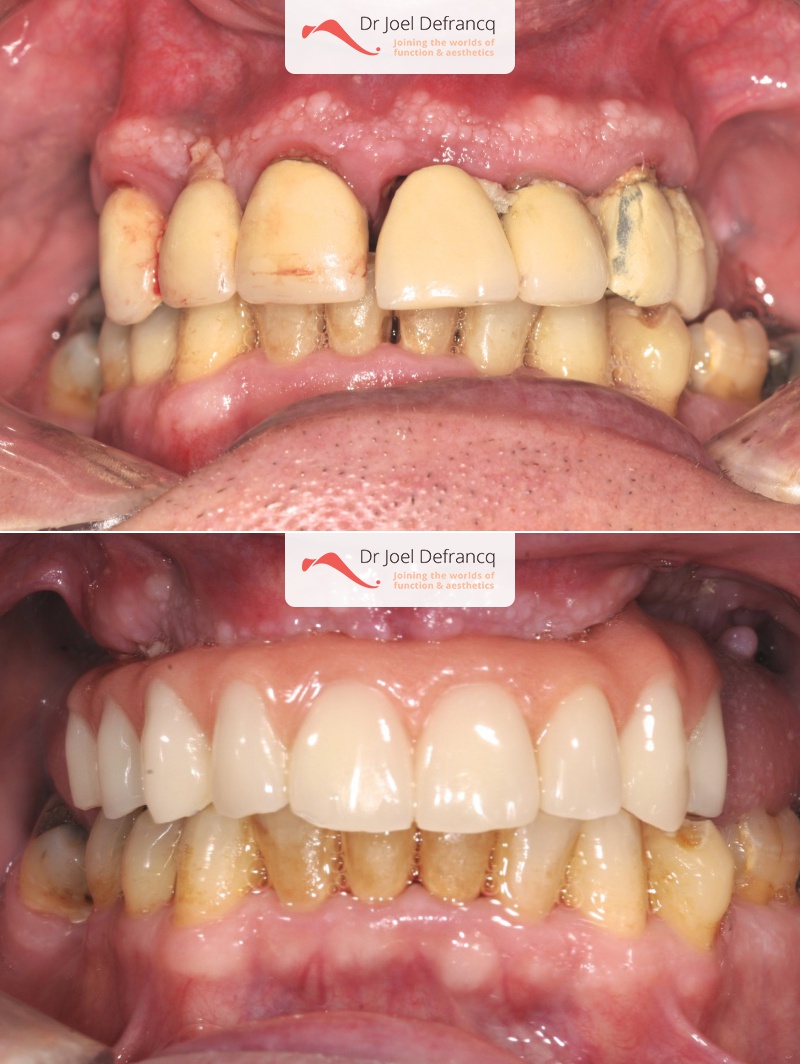

Geert: "all on four" concept met lipofilling en hals liposuctie

Behandeling tandheelkundige implantaten

- Vaste tanden op implantaten (bovenkaak)